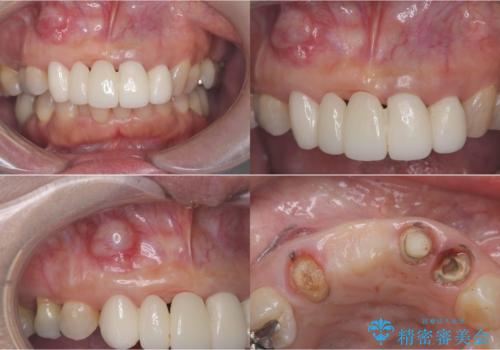

- 歯茎の大きな腫れを主訴に来院された患者様です。前歯5本にはブリッジが装着されていました。レントゲン検査より、右上3番に大きな根尖病巣が認められ、さらに左上1、2番の支台歯にも破折があったため、抜歯を行いました。その後、インプラントを3本埋入し、オールセラミッククラウンのブリッジで補綴しました。

今回のケースでも、しっかりと固定が得られたため、手術は1回で終了し、短期間でオールセラミッククラウンまで装着することができました。患者様も術後の痛みはなく、処方した痛み止めも服用されなかったとのことです。

これだけ大きな病変があったにもかかわらず、痛みがなく短期間で治療が終わったことに加え、被せ物の色も周囲の歯に調和し美しく仕上がったことに、大変ご満足いただけました。